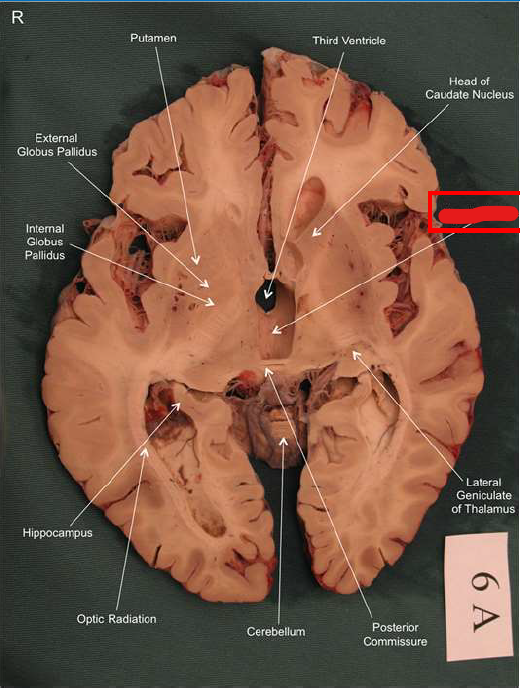

What is this?

hippocampal fornix